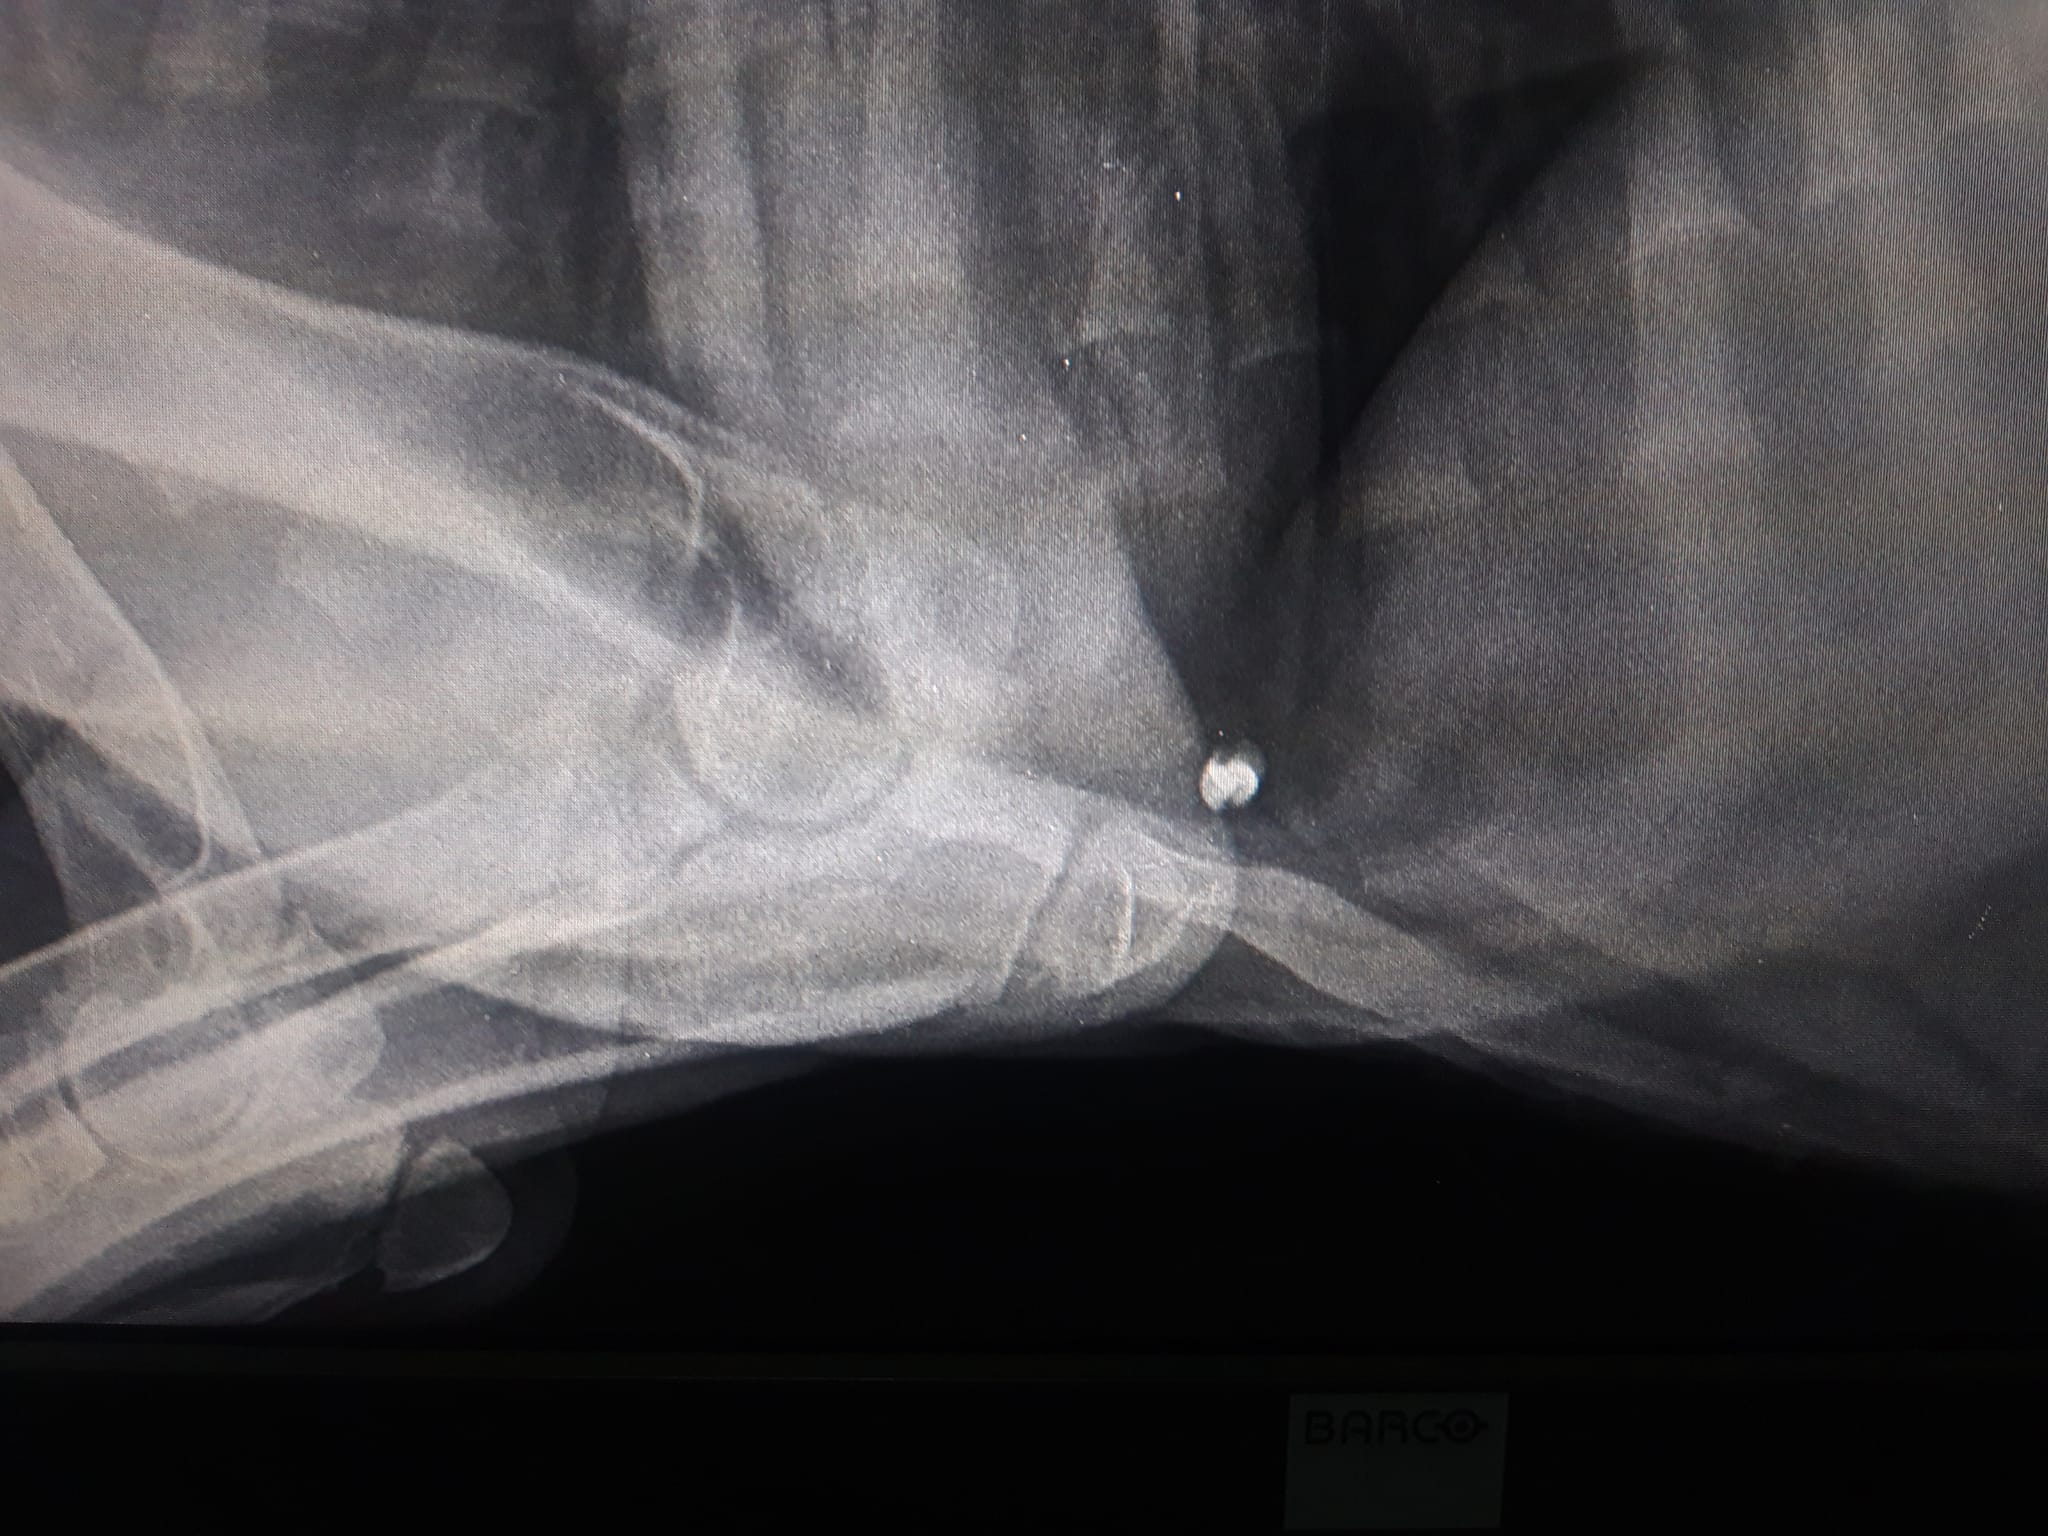

Έκκληση για να καλυφθούν τα έξοδα περίθαλψης ενός κουταβιού που βρέθηκε παράλυτο στα πίσω πόδια έξω από τη Φλώρινα πάνω στις ράγες του τρένου απευθύνει  μέσω facebook η Ναταλία Σαχινίδου. Το ζώο όπως έδειξαν οι ακτινογραφίες έχει πυροβοληθεί με αεροβόλο.

Στις ακτινογραφίες που διενεργήθηκαν ανευρέθηκε βλήμα αεροβόλου όπλου στη θωρακική κοιλότητα οπισθοστερνικά, έντονα ελαττωμένη οστική πυκνότητα ιδιαίτερα στα οπίσθια άκρα, αξιοσημείωτη χαλαρότητα αμφοτερόπλευρα και στα δύο γόνατα πού συνάδει με εικόνα ρήξεως πρόσθιου χιαστού. Στην ουσία όπως θα δείτε και στις ακτίνες μετά από ένα σημείο το στο σχεδόν παύει να υπάρχει, αν όχι από όταν γεννήθηκε τότε στην πορεία το ζώο όσο πιο ατρωφικο γινόταν το οστό τόσο τον οδηγούσε στην κατάσταση που είναι τώρα. Ο Αslan έχει 10% πιθανότητες όχι να περπατήσει αλλά να σταθεί, παρόλα αυτά δεν θα τα παρατήσουμε αφού έχει μια ζωντάνια και μια θέληση για ζωή που θαυμάζω μετά όλο αυτό που του συνέβη στους 5 μήνες της ζωής του ... Θα ακολουθήσουμε φαρμακευτική αγωγή για την θρέψη των οστών και σε 1 μήνα θα πρέπει να πάμε ξανά να δούμε πως πάμε! Για όποιον θέλει να βοηθήσει αυτοί είναι οι λογαριασμοί του κτηνιάτρου κ Νίκου πατσινακιδη.